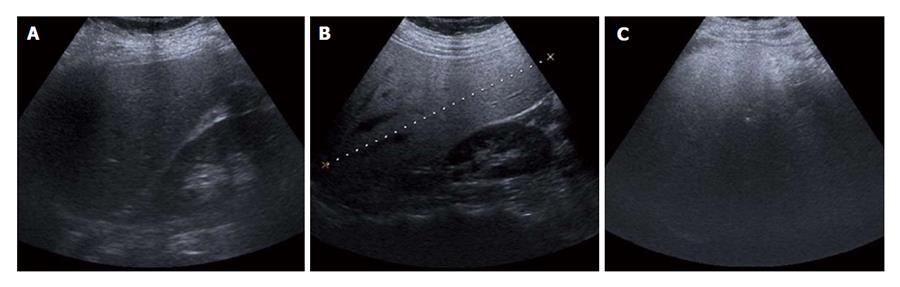

지방간의 초음파적 진단

1. 경도 : 초음파 상으로 가장 가벼운 단계로 콩팥의 바깥 쪽 면과 간의 색이 보통 같아야 하는데, 간의 색이 약간 밝게 보이는 경우를 경도라고 분류합니다.

2. 중등도 : 초음파 상으로는 간으로 들어가는 혈관 중 하나인 문맥의 벽이 밝게 보이는데, 간에 지방이 끼여 문맥의 벽이 밝게 보이지 않을 때 중등도라고 분류합니다.

3. 고도 : 간은 횡격막이라는 가로막의 아래에 위치하고 있는데, 초음파 상으로는 보통 횡격막이 간보다 많이 밝아져 보입니다. 다만 문맥의 벽과 횡격막이 거의 보이지 않을 경우 고도라고 분류합니다.